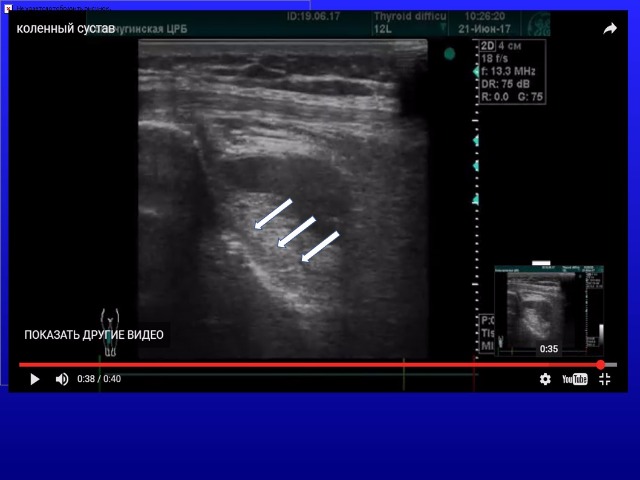

Женщина с патологией опорно-двигательного аппарата - выраженный сколиоз (горб). Травм не было. Занималась ЛФК для позвоночника на коленках. Появилась выраженная боль в суставе.

Я только начинаю смотреть суставы, учусь по книжках. Поэтому прошу не судить строго. Для меня этот случай неясен - прошу помощи и советов

А мне показалось, что выпот преимущественно инфрапателлярно - это не может быть разрыв передней крестообразной связки?

У вас же зона сканированя приемущественно латеральная, вблизи латераного мениска, при чем же здесь инфрапателлярная сумка?!

Что касается передней крестообразной связки, так она опять же выводится из другой позиции!

О повреждении передней КС я бы здесь бы не думал, и вот по каким причинам:

1. Она нечетко, но видна на Вашем видео из переднего доступа, и создается впечатление, что - целая (см. вложенный файл).

2. Разрывы крестообразных связок редко дают такие обильные гематомы и выпоты.

3. Анамнез не тот, как правило, должен быть фактор свежей травмы, причем определенного характера.

4. Ориентироваться на косвенные признаки в отношении крестообразных связок я бы не стал. Проф. Салтыкова В.Г. из ЦИТО настоятельно не рекомендовала сильно фантазировать в заключении в отношении крестообразных связок, которые не очень-то хорошо видны при УЗИ, дабы не дискредитировать наш метод. Я стараюсь так и поступать.

Меня сбило с толку не стандартное сканирование в передне-латеральной плоскости.

Все же для суставов нужно четко выводить стандартные плоскости сканирования, для определения патологического процесса в той или иной сумке или завороте.

Что касается передней крестообразной связки то она видна только при согнутом коленном суставе, то что Алексей указал стрелками мне кажется утолщенная синовия.

Продольная инфрапателлярная проекция была записана при согнутой коленке

Все равно это просто глубокий инфрапателлярный синовит.